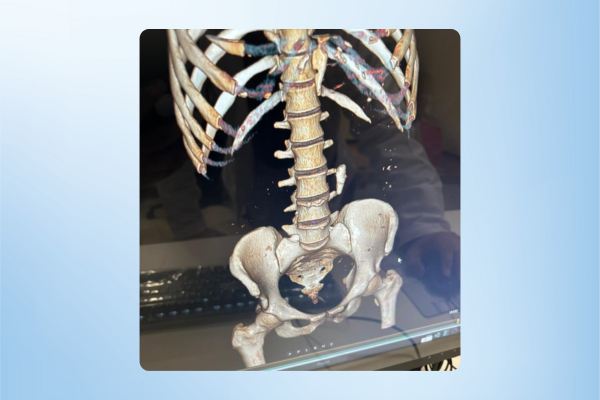

Advancing Urological Oncology: Successful Laparoscopic Nephrectomy

we are committed to offering state-of-the-art care for urological malignancies. Recently, I had the privilege of performing a laparoscopic radical nephrectomy on a 60-year-old lady with a large renal mass.

💡 Highlights of the case:

✅ Minimal blood loss during surgery.

✅ Smooth recovery—patient discharged without complications.

✅ Histopathology revealed clear cell RCC, with negative margins, ensuring she is now cancer-free.

This case underscores the efficacy of minimally invasive techniques, such as laparoscopic and robotic surgery, in managing urological cancers. These approaches offer: